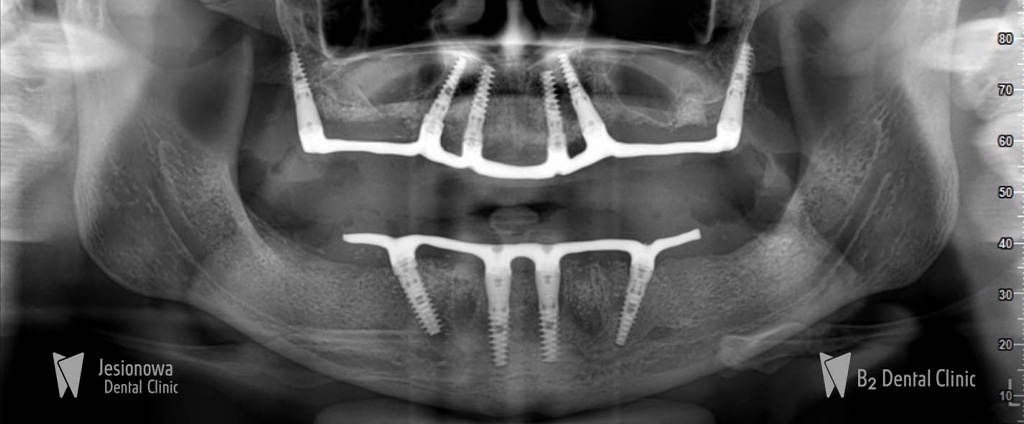

All on 6 + All on 4